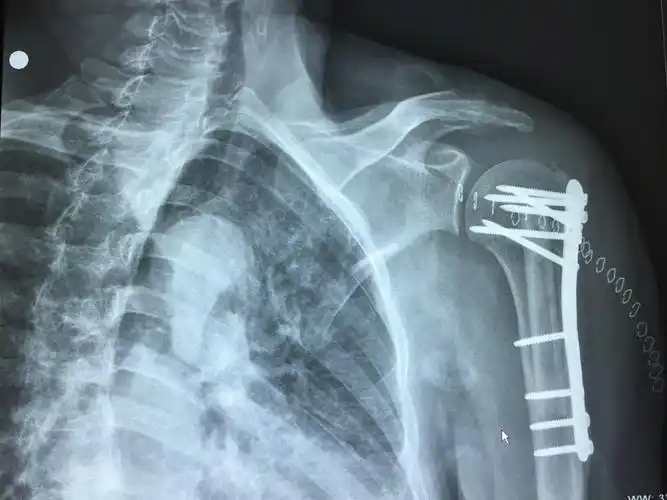

位片投照要点*广东省中医院大学城运动创伤关节镜专科 写美篇肩部创伤